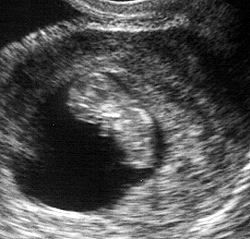

فى الأسبوع السادس من الحمل ونمو الجنين قد لا تزالي غير مدركة بعد بأنك حامل وستكونين أم في وقت قريب.

لكن الجنين ينمو بشكل طبيعي بداخلك ويبدأ القلب في التكوين ويكون حجمه مثل حبة الذرة ويبدأ بالفعل في النبض وضخ الدم. ينقسم القلب إلي أجزاء صغيرة، وتبدأ ضربات القلب في الانتظام بشكل أكبر بعد ذلك. أصبح الآن حجم الجنين أو الحميل كما يسمى في هذه الفترة 0.6 سم ويشبه جنين الضفدع. يحدث نمو جيد وسريع في هذا الأسبوع حيث تبدأ الأعضاء الأساسية في النمو، مثل الكليتين والكبد. أما عن الأنبوب والذي بدأ يتكون في الأسبوع الرابع كما ذكرنا والذي يصل المخ بالعمود الفقري فيبدأ هذا الأسبوع في الانغلاق.

تبدأ براعم الأطراف في الانشقاق والخروج (الأذرع ، الأرجل) وتبدأ هذه الأطراف الصغيرة في تكوين الأذرع والأرجل فيما بعد. تستمر المعدة في التكوين مع تكوين الزائدة الدودية.

أما أسفل المنطقة التي ستكون الفم فيما بعد يبدأ جزء صغير جداً من الرقبة والفك السفلي في النمو. وبالنسبة للشكل الخارجي للوجه فهو ينمو منذ بداية هذا الأسبوع، فيمكن التعرف علي مكان فتحات الأنف وبداية ظهور الشكل الأولي لشبكية العين.